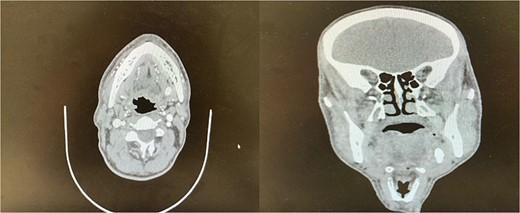

The accuracy of navigation was periodically verified by referencing stable bony landmarks, such as the mental foramen and mandibular condyles, with the navigation probe. Realignment was conducted as needed to ensure consistent anatomical mapping and precise localization of the submandibular stone (Fig. 2). After surface registration, a 1 cm mucosal incision was made intraorally at the nearest point indicated by the navigation pointer, parallel to the anticipated course of the Wharton duct. Blunt dissection was performed to expose the duct, with navigation toward the stone guided by the system. Great care was taken to protect the lingual nerve throughout the procedure. The depth of dissection was gradually advanced by periodically verifying the position with the navigation pointer probe (Fiagon) to maintain precision. During dissection, the stone was accurately located within the gland parenchyma using real-time visualization, and it became palpable, distinguished by its unique color and texture (Fig. 3). The stone was fragmented and removed in pieces because it was fixed (Fig. 4). The surgical field was flushed with saline to remove any residual stone debris, and the incision was closed with 4/0 Vicryl, which is an absorbable suture.

Intraoral extraction of the submandibular gland stone during the procedure.